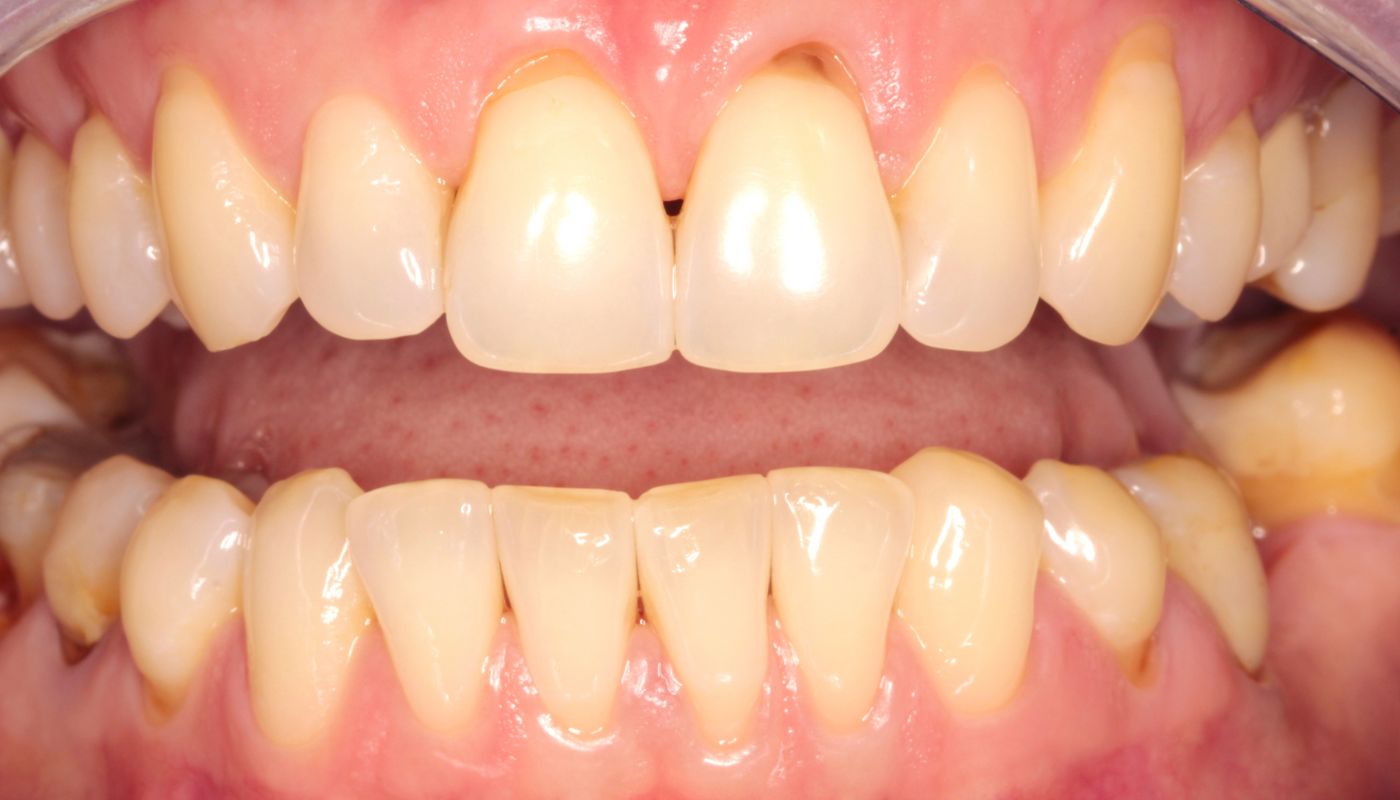

Powód kosmetyczny, to drugi bardzo częsty powód pojawiania się pacjentów w gabinecie stomatologicznym. Obnażone szyjki zębowe oraz odsłonięcie korzenia zęba wpływa na nieestetyczne wydłużenie się, oraz ich obniżanie w dziąśle. Nie tylko pogarsza to ogólny wygląd uśmiechu, ale również może doprowadzić do innych zaburzeń zgryzowych.

Recesja dziąseł, czyli odsłonięte szyjki zębowe mogą pojawiać się z wielu powodów. Należy wyszczególnić recesje spowodowane przez czynniki patologiczne wynikające z namnażających się bakterii oraz recesje o uwarunkowaniach anatomicznych, wynikających z budowy zębów, kości, wady zgryzu oraz cienkiego fenotypu dziąseł.

Problem odsłoniętych szyjek zębowych często zależny jest od wady zgryzu. Może być konsekwencją nieprawidłowego ustawienia zębów, ich nadmiernego stłoczenia czy nachylenia w kierunku wargowym.